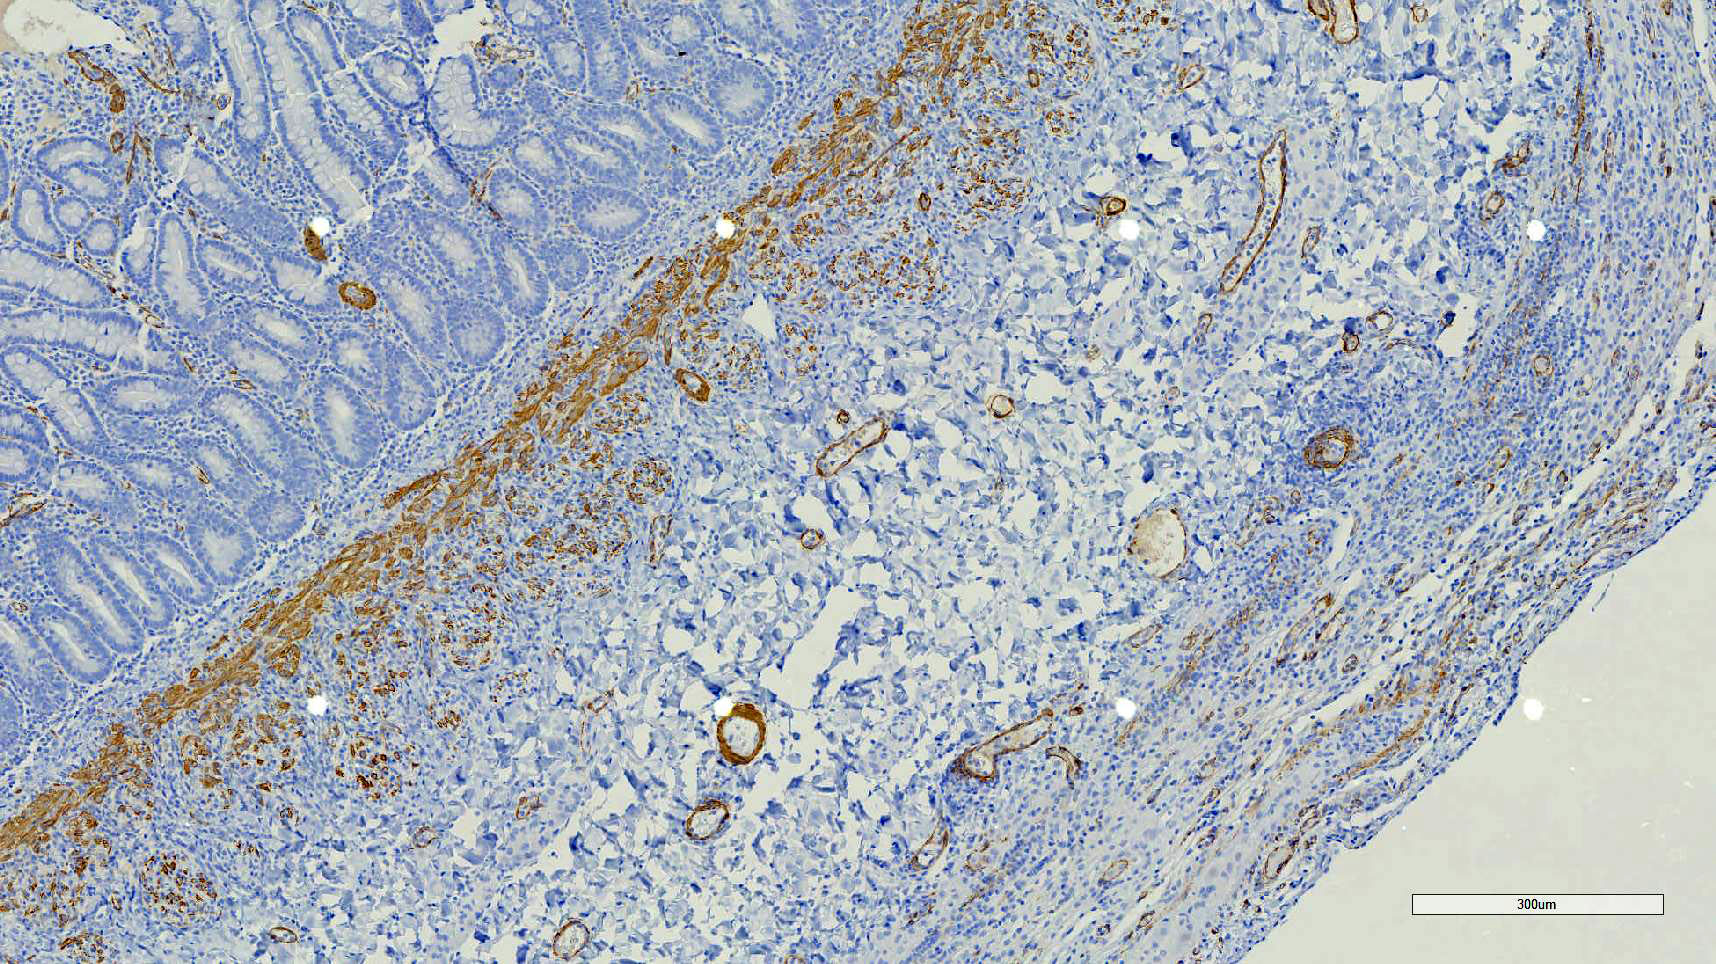

Duodenum, jejunum and ileum: Diffusely throughout the sections, there is partial to complete loss of the leiomyocytes of the outer and inner muscularis, which are multifocally replaced by loose fibrous connective tissue (fibrosis). The remaining smooth muscle is infiltrated by large numbers small and intermediate lymphocytes, few macrophages and neutrophils. The same inflammatory infiltrate is present throughout the muscularis mucosae. Remaining leiomyocytes have pale, frequently vacuolated cytoplasm. In the submucosa, muscularis and serosa there are small to moderate numbers of perivascular lymphocytes. Small lymphocytes, and infrequently neutrophils, surround or infiltrate the myenteric and submucosal ganglia, though neurons do not exhibit degenerative changes. The lamina propria contains a markedly increased number of lymphocytes, plasma cells and a mildly increased number of eosinophils. The epithelium is diffusely overlain by myriad bacterial rods. The serosa is mildly expanded by increased clear space (edema) and is lined multifocally by markedly hypertophied mesothelium. In the stomach a similar process is observed but restricted to the outer aspect of the muscularis with a patchy/multifocal distribution and sparing of the muscularis mucosae. (section not submitted).

Duodenum, jejunum and ileum: Severe, diffuse, chronic lymphocytic leiomyositis with severe muscularis atrophy; marked, diffuse, chronic lymphoplasmacytic enteritis.

Microscopic findings reported for this condition consist of mild to marked mononuclear infiltrate, myofiber degeneration and fibroplasia or fibrosis centered within the muscularis propria of the stomach, small and large intestinal wall with the jejunum being the most severely and chronically affected segment.7,15 In early lesions the inflammation and smooth muscle degeneration are segmental, random between the outer and inner muscularis layers and sparing of the muscularis mucosae.15 Concurrent cecal involvement leading to impaction has also been described.5 Consistent histologic findings included T-lymphocyte inflammation within the muscularis propria with relative sparing of the mucosa, submucosa and neural plexuses.14 In one case report the inflammatory infiltrate was predominantly of B-lymphocytes and featured extensive angiogenesis.6 Leiomyocytes appear to be the target of the inflammation given the presence of various stages of degeneration leading to complete myofiber loss in chronic stages of the disease. Superficial inflammation is a frequent secondary finding in CIPO and has been associated with bacterial overgrowth, which were changes observed in this case.6 Neuropathy has not been a feature in most reports of canine CIPO. Inflammatory cells obscuring the myenteric and submucosal plexuses in this case were considered an extension from the neighboring inflammation as no degenerative changes were observed in the neurons. Myenteric ganglionitis has, however, been reported occurring concurrently with leiomyositis.10